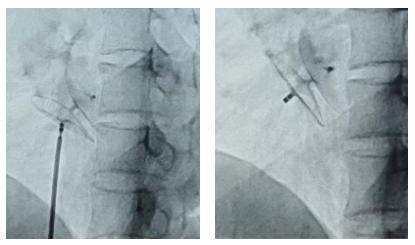

明确诊断后,考虑手术风险和难度高。内科医疗团队进行周密的术前讨论和充分准备,取得患者及家属同意后,为患者实施经导管卵圆孔未闭封堵术。在X线的实时引导下,精准定位未闭合的卵圆孔,释放封堵器,一气呵成完成闭合。整个手术用时约30分钟,患者全程保持清醒,创伤不过针孔大小。术后第二天,患者即可下地行走。